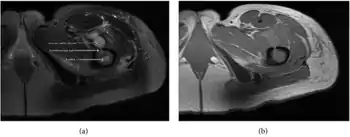

a,b) MRI showing the Brodie's abscess in the left proximal femur